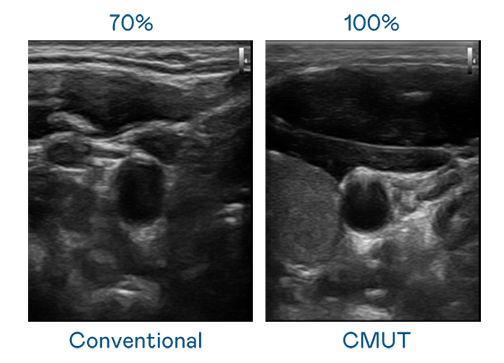

CMUT 技术是一种用电容式微机电元件来产生超音波讯号的技术。与传统 PZT 压电式技术相比,CMUT 频宽增加 30%,更宽频的超音波讯号让影像解析度大幅提升,是实现高影像品质医疗超音波扫描、促进精准医疗发展的关键技术。

超音波影像的解析度高低,首先取决于探头能发出的讯号频宽。AC米兰 CMUT 可提供高清晰的超音波讯号,提供高频宽、高灵敏度、影像纹理细节更高的超音波影像,协助医护人员缩短影像判读时间及利用精准的医疗影像进行诊断。